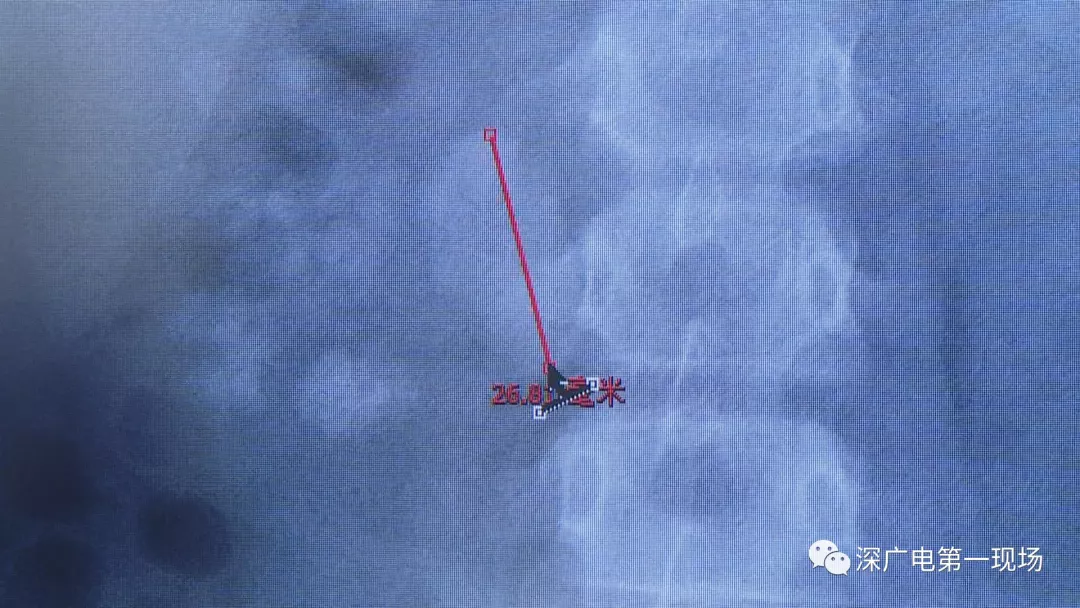

在X光圖像下,醫(yī)生發(fā)現(xiàn)小軒的雙側(cè)腎臟都內(nèi)藏乾坤,密密麻麻的分布著大小不等的結(jié)石。

小軒這種情況,其中,最大的結(jié)石長約2.7厘米,寬約1.7厘米,體積堪比鵪鶉蛋,不但造成了尿路堵塞,還導(dǎo)致了右腎中度積水。